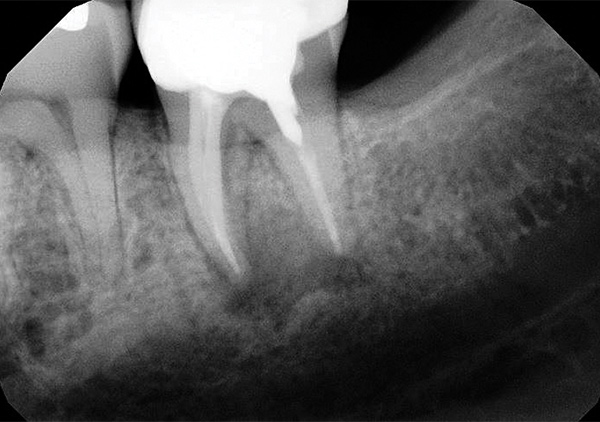

The patient was given postoperative instructions and medications (amoxicillin 500 mg, ibuprofen 600 mg, and chlorhexidine mouth rinse). He returned to the clinic 5 days post-treatment for suture removal and evaluation. No radiograph was taken at the 5-day postoperative recall visit. The patient presented with tooth No. 18 intact and slightly mobile and reporting slight discomfort of the surgical area. At a 2-month recall tooth No. 18 was found to be asymptomatic and fully reintegrated into the socket (Figure 9). Mobility and periodontal probings were within normal limits.

Periapical radiograph of tooth N o. 18 at

2-month recall appointment.

Fig 9.